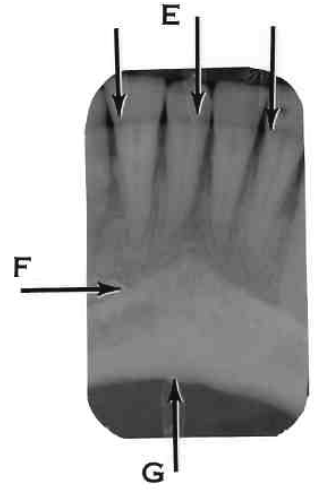

11. Which option is indicated by arrow E?

13. Arrow E showing which anatomical structure?

14. What is showing by E?

15. Arrow F showing which anatomical structure?

16. What is showing by E?